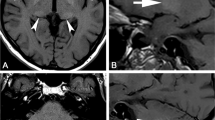

The T1 hyperintensity of the DN in an unenhanced MRI scan was initially reported as potential grey matter damage in secondary progressive multiple sclerosis (MS) [27, 28] and was also found in patients who had received previous brain radiotherapy [29]. At the time of publication of these studies, Gd had not been considered as a possible confounder for these imaging findings, and instead was attributed to the conditions under study. In 2014, this imaging finding and high T1-signal intensity in the GP were found to be positively correlated with the number of administrations of GBCA [30] with none of the patients having a diagnosis of MS. Similar findings have been replicated in a number of retrospective imaging studies in both adults and children, drawn from a variety of populations and using multiple different agents. These imaging studies are summarized in Table 1. Overall, the majority of studies demonstrated an increase in the signal intensities of DN and GP with linear agents but not with macrocyclic agents and the increase is correlated with the number of doses. Patients with MS feature in multiple studies, and this group is subject to specific concerns over potential long-term effects, since this population is diagnosed at a young age and has a long life-expectancy [31].

Only two publications have reported more widespread imaging changes in patients who have received unusually numerous linear GBCA administrations. In patients who received >35 GBCA administrations, T1 hyperintensity has been found in other brain regions (substantia nigra, pulvinar, red nucleus, colliculi, superior cerebellar peduncle, caudate nucleus, thalamus and putamen) [32], and in the cortex of the pre-central and post-central gyri and around the calcarine sulcus [33] following at least 86 administrations (mostly linear).

More recently, quantitative MRI approaches have been applied using T1 relaxometry and quantitative-susceptibility mapping (QSM). The quantitative approach has shown a correlation between DN R1 relaxation and previous GBCA exposure [34]. As expected, QSM echoes the findings of T1 studies, namely that DN susceptibility is increased after administration of linear GBCAs [35]. Conversely, no signal alterations were found in patients who received large total doses of macrocyclic GBCAs (mainly gadobutrol) [36, 37]. Overall, retrospective studies in neurological pediatric patients replicate the findings observed in adults, namely that T1 hyperintensities in the brain are observed following administration of linear GBCAs [38,39,40] but not macrocyclic GBCAs [41, 42]; however, three imaging studies stand out as exceptions to reporting imaging changes with macrocyclic GBCAs. One study [43] claimed a change in DN signal intensity following use of macrocyclic agents, although the study had limitations in its design and did not completely rule out confounding factors (including prior exposure to linear agents) [44]. Later studies have not shown similar findings [45,46,47].